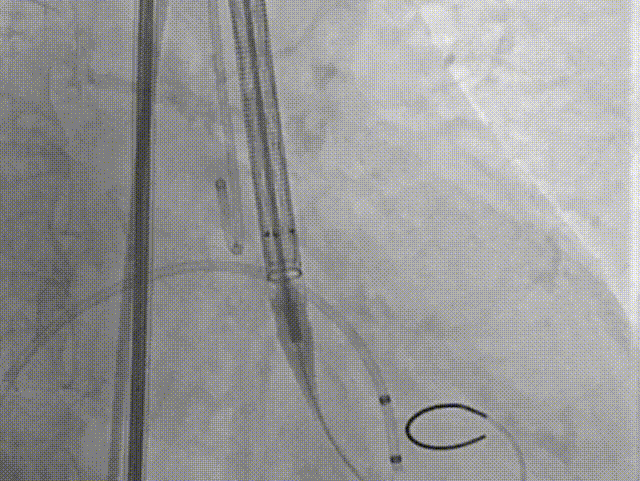

手术过程

主动脉根部造影

18球囊预扩张

瓣膜定位

瓣膜释放过程

瓣膜形态

18球囊后扩张

瓣膜最终形态